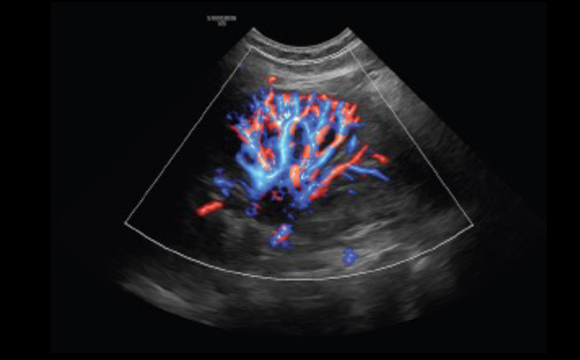

Visualizzazione tridimensionale del flusso ematico

LumiFlow™ ¹ è un software per la visualizzazione tridimensionale del flusso ematico, che consente di individuare intuitivamente la struttura dei vasi sanguigni di qualunque dimensione.

Rene S-Flow™ con LumiFlow™ b